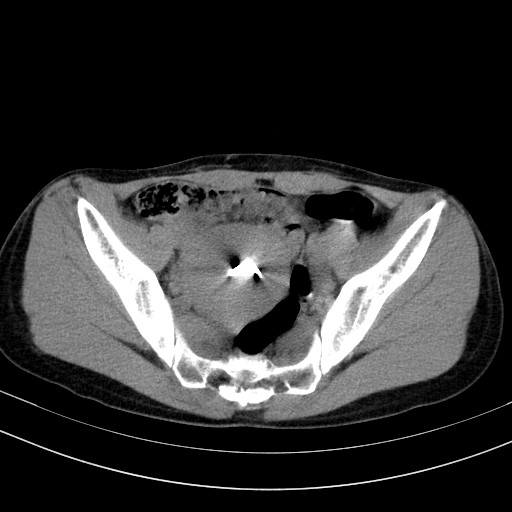

以下是引用卜一在2009-4-7 5:08:00的发言:[br]宫颈癌可能。支持!

以下是引用随光逐影在2009-4-7 8:17:00的发言:[br]考虑宫颈占位性病变(宫颈癌?);建议行进一步检查。

以下是引用jiangjing在2009-4-7 16:46:00的发言:[br]宫颈增大,结构不清,右侧附件区可疑囊样占位,建议增强及mri 检查